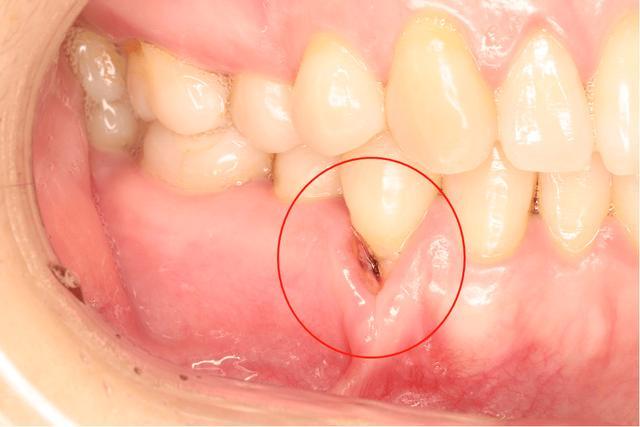

1、牙齦紅腫:牙周炎患者的牙齦組織通常會變得紅腫。

2、牙齦出血:刷牙或咬硬物時容易出血。